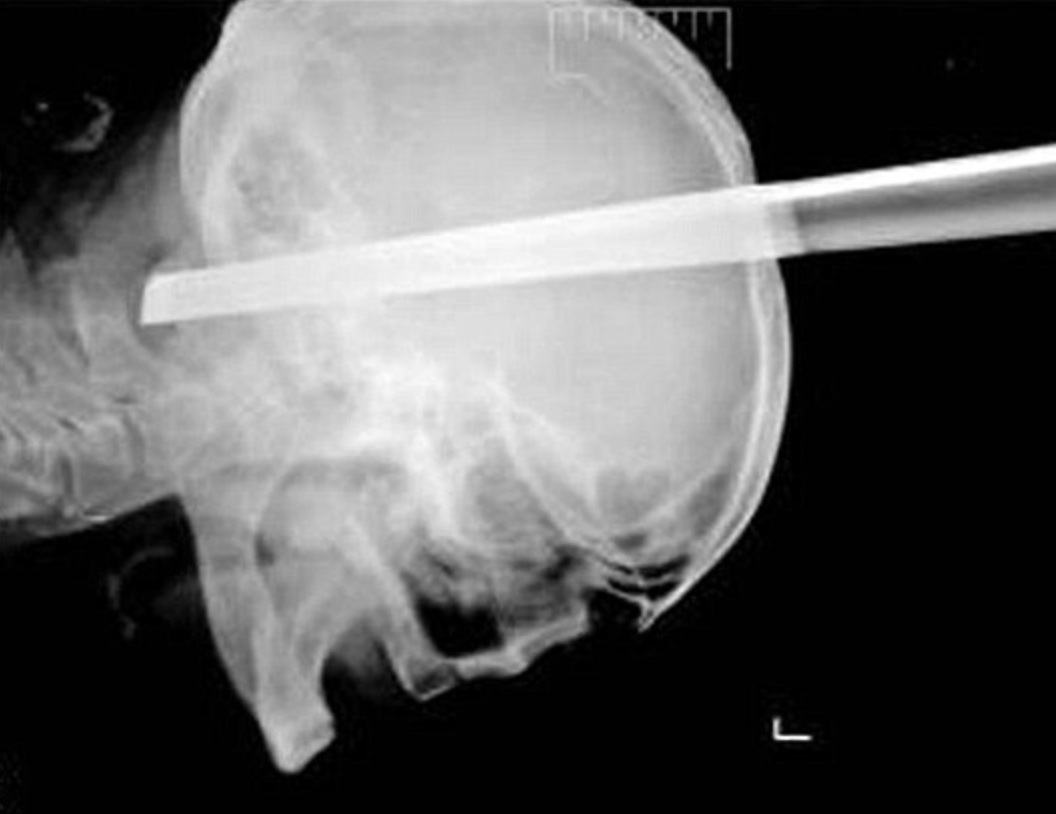

14. Falling On A Drill

A construction worker named Ron Hunt fell from a ladder whilst he was working. At that moment in time, he had been drilling. He fell, onto the drill, which went piercing through his eye socket and out the back of his head. Spectacularly he managed to survive the incident.Advertisement